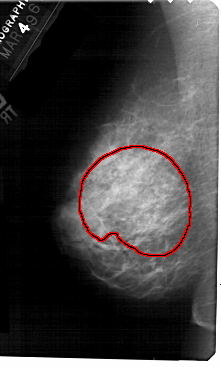

A_1559_1.LEFT_MLO

LEFT_MLO LINES 5491 PIXELS_PER_LINE 3301 BITS_PER_PIXEL 12 RESOLUTION 43.5 OVERLAY

FILE: A_1559_1.LEFT_MLO.OVERLAY

TOTAL_ABNORMALITIES 1

ABNORMALITY 1

LESION_TYPE CALCIFICATION TYPE AMORPHOUS DISTRIBUTION REGIONAL

ASSESSMENT 4

SUBTLETY 3

PATHOLOGY BENIGN

TOTAL_OUTLINES 1

BOUNDARY